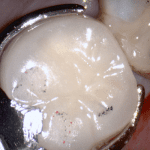

This case was scanned by two different scanners. Once by the Medit i500 and another time with the Aoralscan. Both the meshes are included so you can compare the two. It was scanned to deliver a case that retrofits a partial denture